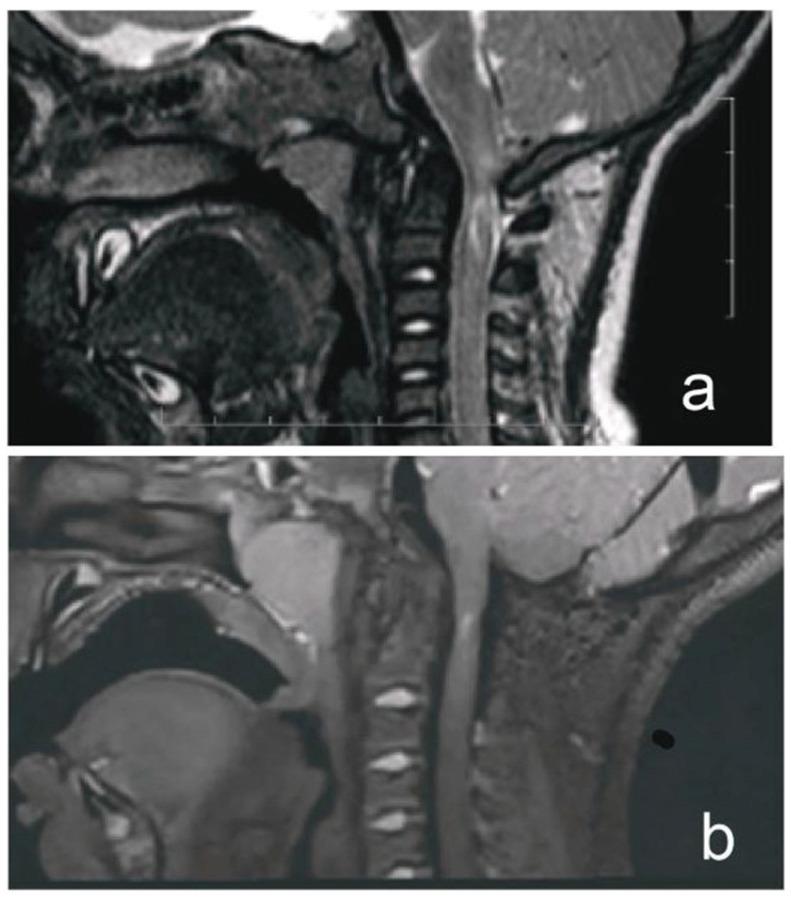

A 1-year-old boy with achondroplasia presented with acute tetraparesis after a whiplash injury. Initial craniocervical computed tomography demonstrated a reduced volume of the posterior fossa, foramen magnum stenosis, and ventriculomegaly, without any fractures or dislocations. Moreover, magnetic resonance imaging (MRI) revealed pathological signal changes in the medulla oblongata, cervical spinal cord in segments C1 and C2, and the posterior atlantoaxial ligament. After initial conservative therapy and head immobilization using a soft cervical collar, partial remission of the tetraparesis was achieved. Two weeks post-injury, microsurgical posterior fossa decompression extending to the foramen magnum and C1 laminectomy was performed under general anesthesia with intraoperative neuromonitoring. Following an unsuccessful intubation attempt using a fiberoptic bronchoscope, successful airway management was achieved using a combined technique incorporating video laryngoscopy. Venous access was secured under ultrasound guidance. The patient exhibited complete remission of neurological symptoms by the third postoperative month during follow-up.

一名1岁软骨发育不全男孩在挥鞭样损伤后出现急性四肢瘫。最初的颅颈计算机断层扫描显示后颅窝容积减小、枕大孔狭窄和脑室扩大,无任何骨折或脱位。此外,磁共振成像(MRI)显示延髓、C1和C2节段的颈脊髓以及寰枢后韧带存在病理信号改变。在最初采用保守治疗并使用软颈托固定头部后,四肢瘫部分缓解。受伤两周后,在术中神经监测下于全身麻醉下行后颅窝减压术,范围延伸至枕大孔并进行C1椎板切除术。在使用纤维支气管镜插管尝试失败后,采用视频喉镜联合技术成功实现气道管理。在超声引导下确保了静脉通路。在随访期间,患者术后第三个月神经症状完全缓解。